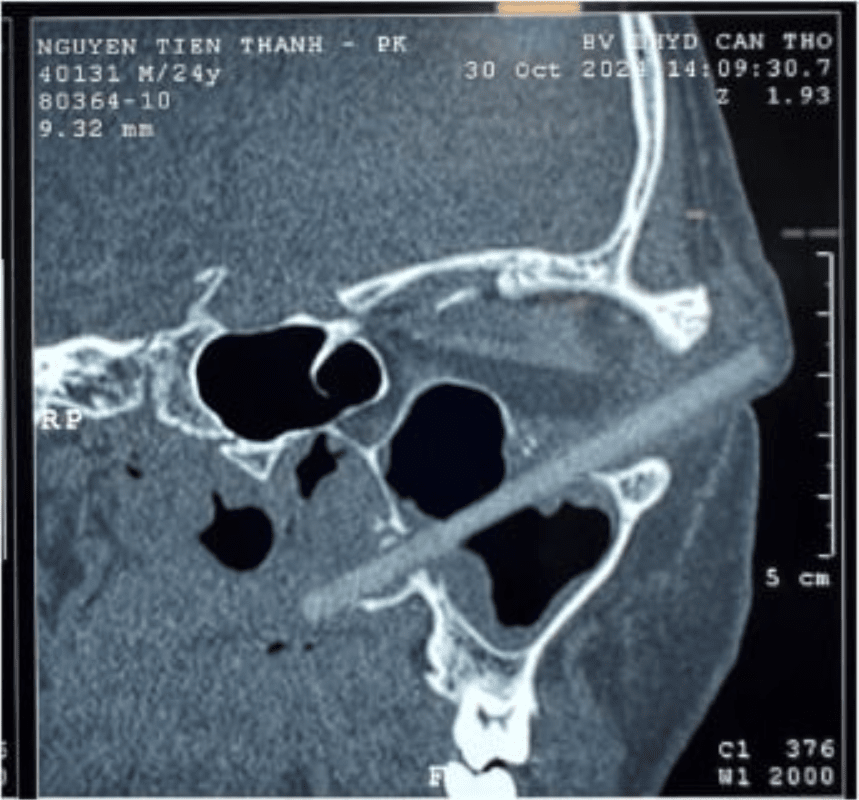

В университетской клинике, куда в итоге пришел больной, ему провели КТ, которое показало, что в глазнице застряло инородное тело длиной 9 сантиметров. Посторонним предметом оказалась деревянная палочка для еды.